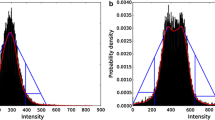

Segmentation of the entire kidneys and differentiation of their internal structures were performed in 12 healthy volunteers based on non-contrast-enhanced T1- and T2-weighted MR images. Two data sets (each acquired in one breath-hold) were co-registered using a rigid registration algorithm compensating for possible breathing-related displacements. An automatic algorithm based on thresholding and shape detection segmented the kidneys into their compartments and was compared to a manual labeling procedure.

The resulting kidney volumes of the automated segmentation correlated well with those created manually (R 2 = 0.96). Average volume errors were determined to be 4.97 ± 4.08 % (entire kidney parenchyma), 7.03 ± 5.56 % (cortex), 12.33 ± 7.35 % (medulla), and 17.57 ± 14.47 % (pelvis). The variation of the kidney volume resulting from the automatic algorithm was found to be 4.76 % based on the measuring of one volunteer with three independent examinations.